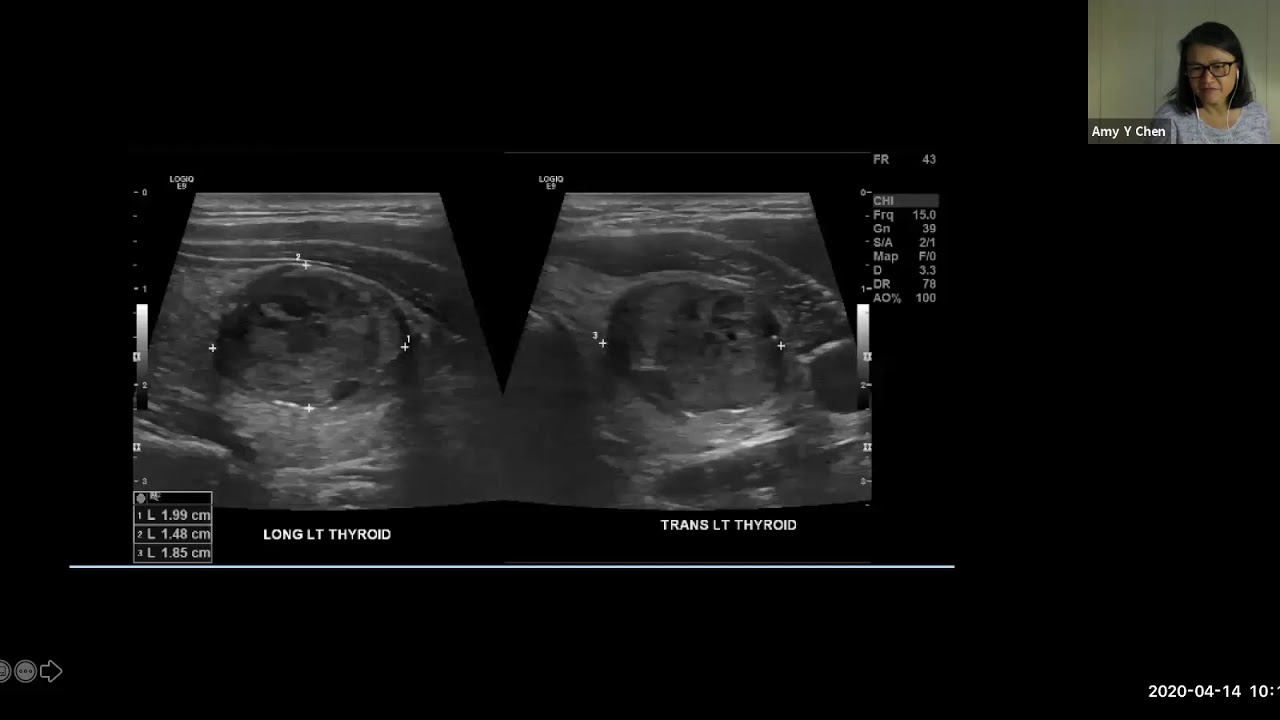

Thyroid Case Presentations Dr Amy Chen Youtube April 14, 2020 zoom lectureentcovid.med.uky.edu. Precision medicine has changed everything for thyroid cancer treatment. gone are the days when everyone with a thyroid nodule or cancer diagnosis automatically had their entire thyroid removed.